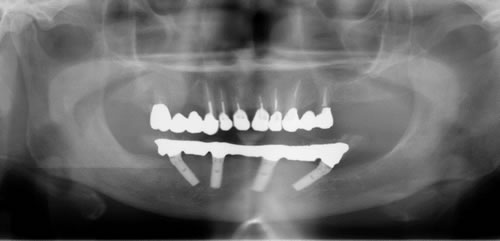

奥歯に骨がないので、オールオン4で即時荷重(インプラント手術をした日に仮歯がはいる)をおこないました。

治療後